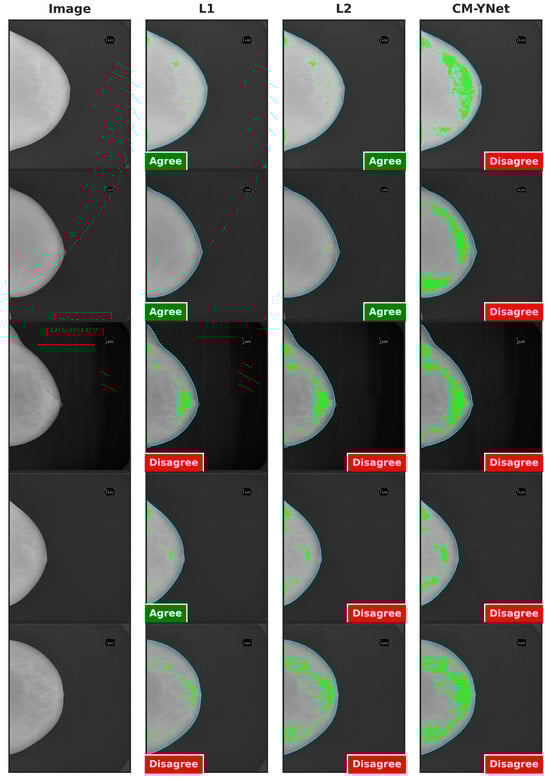

Figure 15 provides examples of segmentations produced by CM-YNet where V2 expressed disagreement both times the same segmentation was shown. These disagreements occurred in a total of 14 images. Specifically, V2 assigned 12 cases as oversegmented and 2 cases as undersegmented.

Figure 15.

Examples of segmentations that were shown twice to V2 to analyze intra-observer variability. In these examples, V2 indicated disagreement with CM-YNet on both occasions.

Figure 16 illustrates two examples where V2’s decisions varied depending on the order in which the segmentations were presented. In the example in the first row, V2 initially marked the first segmentation (L1) as correct. However, when the next two segmentations (CM-YNet and L2) were shown, both with identical segmentations (DSC = 1), V2 changed his decision to oversegmented for CM-YNet and then correct again for L2. In the example in the second row, V2 indicated the first segmentation (CM-YNet) as versegmented but later marked L1 as correct and L2 as oversegmented. Similar to the first example, L1 and L2 had identical segmentations (DSC = 1).

Figure 16.

Examples of segmentations where V2 assigned different labels despite identical segmentations (DSC = 1): L2 and CM-YNet in the first row, and L1 and L2 in the second row. Although the visual layout follows a fixed column order (original image, L1, L2, and CM-YNet), the validator viewed the segmentations in a different sequence. In the first-row example, the order of appearance was L1, CM-YNet, and L2. In the second-row example, the order was CM-YNet, L1, and L2.

Figure 17 presents the agreement percentages between V2 and each labeler as a function of their order of appearance. Notably, the agreement with CM-YNet improved significantly, rising from 77.46% when CM-YNet was presented first to 91.41% when it appeared last. This upward trend in agreement was not observed for L1 and L2. For these labelers, agreement percentages increased when they appeared second then decreased again when they were shown third, showing no clear pattern. Therefore, even though the intra-observer variability indicates more inconsistency for V2 compared to V1, it appears that V2 maintained a consistent criterion over time. The inconsistencies found were more likely due to the inherent intra-observer variability that is well-known for this type of segmentation tasks, especially in the medical domain.

Figure 17.

Agreement percentages between V2 and each labeler based on the order in which segmentations were presented. The first row shows the results when the segmentations were presented first for a given image. The second and third rows correspond to cases where the segmentations appeared second and third, respectively.